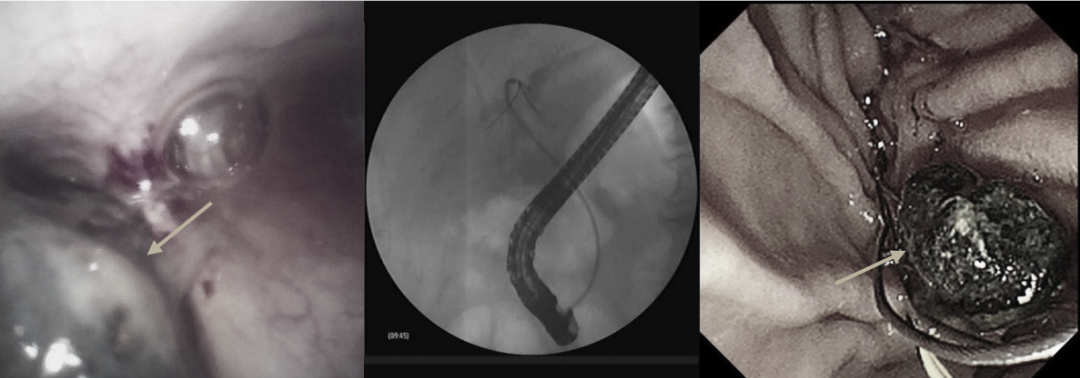

术中胆道子镜见左肝内胆管多发乳头状增生,子镜直视下精准活检(3处箭头所示)

时间在一分一秒地过去,是结石已经自己排掉?还是结石躲藏在更深处常规ERCP无法发现?考虑病人高龄,身体条件差,一旦漏掉结石再次发病后果不堪设想,团队马上启用备用方案,应用胆道子镜探寻结石!胆道子镜进入胆管内,首先于胆囊管搜寻,未见结石。然后进入肝内胆管一级分支亦未发现结石,紧接着子镜进入狭小的二级胆管逐一排查,终于发现,结石已偷偷地从胆总管“逃”到了肝内胆管!紧接着一个难题是如何把结石取出,传统的ERCP手术对位于肝内胆管的结石几乎束手无策,普通ERCP手术器械在如此狭小的空间无法施展。经过讨论,团队改变治疗策略,决定用子镜下微细网篮尝试取石,通过在狭小的空间内仔细观察、谨慎处理、反复调整,历时半个多小时的精细操作,终于将结石拖入胆总管,随后成功取出了结石!

640?wx_fmt=png&from=appmsg

子镜下所见结石位于肝内胆管,箭头所示结石(左图),子镜下尝试肝内胆管取石(中图),成功取出胆管结石,箭头所示取出结石(右图)